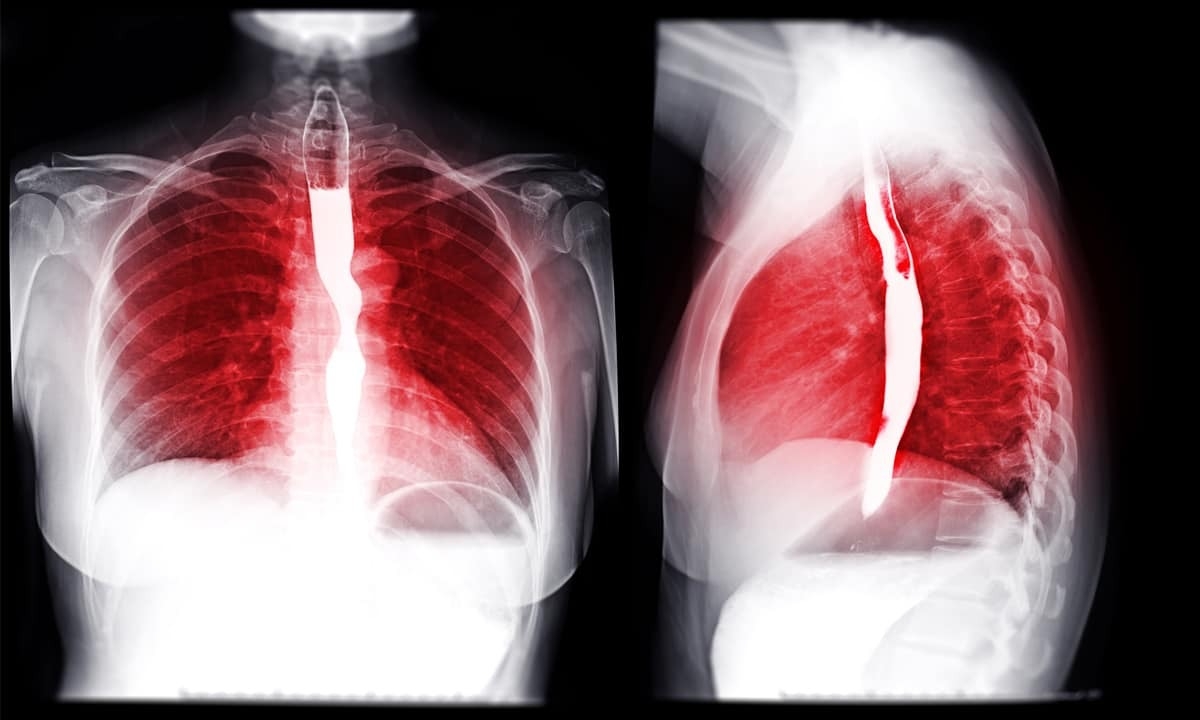

A barium swallow test, also sometimes referred to as an upper GI series, is an imaging test performed by a radiologist that uses X-ray and fluoroscopy technology. X-rays provide doctors with a series of radiographic images that help visualize different sections of the gastrointestinal tract. A key component of a barium swallow is the introduction of a contrast medium into the body; such substances serve to increase the contrast between structures and fluids in the body. When used alongside an X-ray, the radiologist can get a much clearer picture of any abnormalities that are present.

One of the most common radiocontrast agents used for such tests is barium sulfate. Barium sulfate is an inorganic compound that has many uses in industry and technology. However, because it is insoluble in water, it also cannot be absorbed by the body. This means it lingers and its density makes it impenetrable to X-rays; as a result, it can coat various internal surfaces inside the body and make them visible on radiographs. Prior to the X-ray, the patient is asked to drink a barium sulfate suspension that easily coats the pharynx, esophagus, stomach, and bowels.

Unlike endoscopy, which typically involves twilight sedation and feeding the endoscope down your esophagus, the barium swallow test (also known as a barium esophagram) is relatively easy to perform. You’re generally instructed to fast the night before the test is scheduled; in some cases you may be asked to avoid particular medications. The barium solution is a chalky mixture that can be unpleasant in terms of taste. A series of X-ray images are then taken as the liquid moves through your digestive system and coats various surfaces. The radiologist will be reviewing the images to look for any abnormalities.